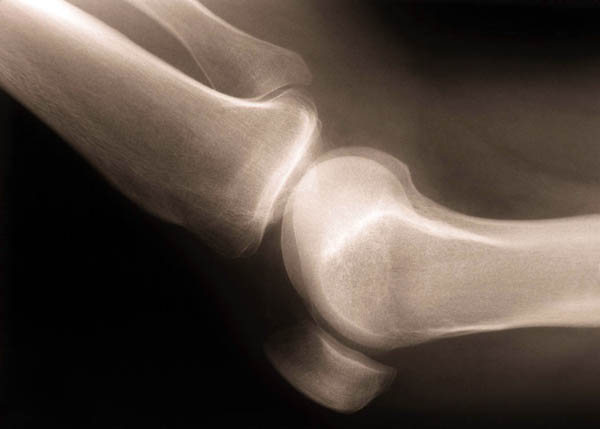

Knee Pain

Mechanical knee pain is caused by the overuse injuries, wear and tear, referred pain, and bursitis and tendonitis, as well as partial/complete tear of the knee cartilage, partial/complete tear of the knee ligaments, patella tracking problems.

Cartilage Tears – This often occurs in sports injuries or bad falls. You can also get wearing of the cartilage which can give microscopic tears in it with road running, excessive cycling, and work related stress (i.e. plumbers, builders).

Ligament Tears – These are relatively uncommon and usually require a severe sports injury or direct impact injury or a twisting injury. Most of these injuries can heal with time and rehabilitation of the knee stabiliser muscles can be very beneficial but some will require surgical repair such as a tear in the Anterior Cruciate Ligament.